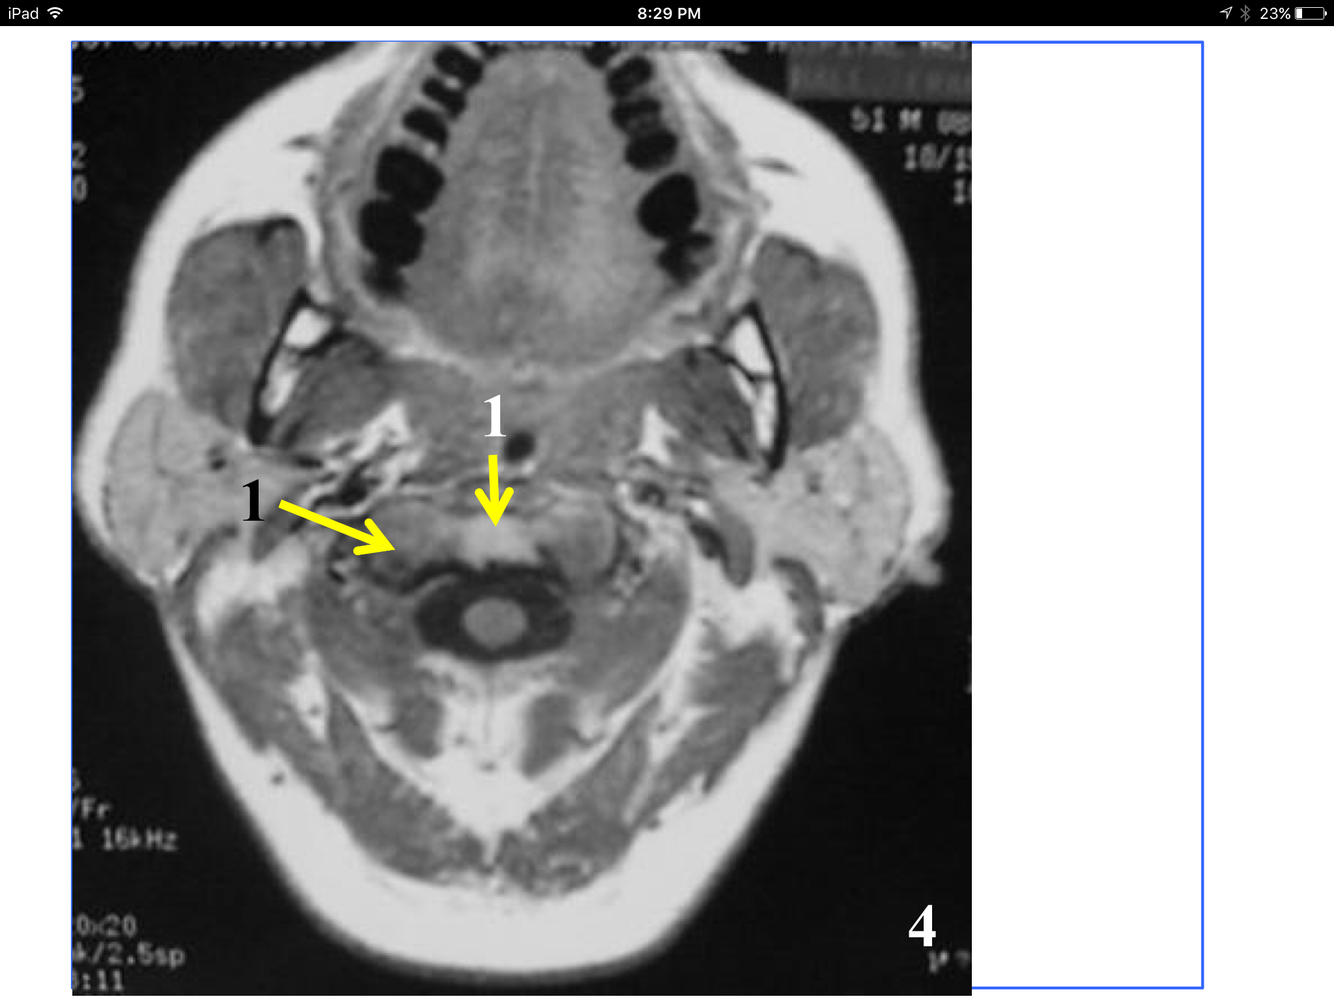

*Appears as streak as it heads fo rmidline in front of the medulla oblongata, to join the Rt vertebral and form the basilar A at the inferior and anterior to the pons.

** At the foramen magnum, entering the posterior fossa of the cranium.

*near the atlantooccipital joint